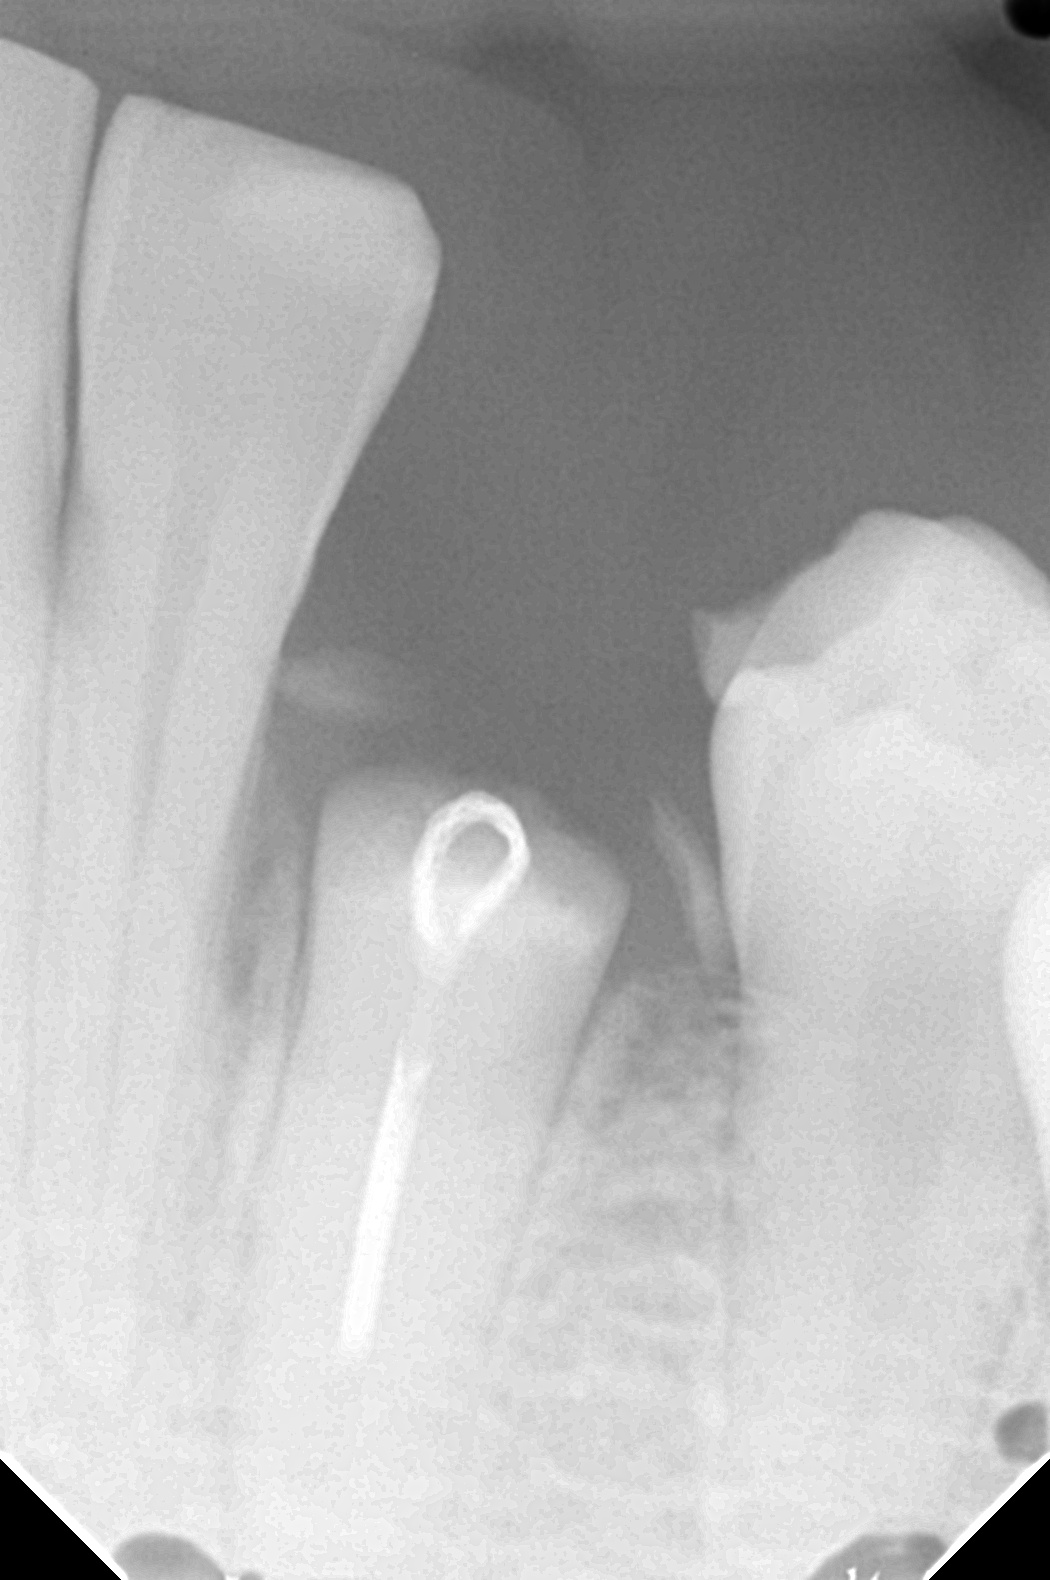

下のレントゲン写真は、歯根に輪っか状の器具(フック)を装着した状態です。レントゲンでは歯茎は映りませんが、歯根が骨のギリギリまで折れてしまっていることがわかります。ここからゴムやワイヤーの力を使って、少しずつ歯根を歯ぐきの外に引き出していきます。